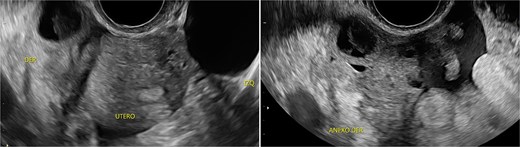

Stage III pelvic inflammatory disease (PID) was suspected based on ultrasound (Figs 1–3) and gynecological examination, which revealed mild bulging of the right lateral fornix, cervical motion tenderness, and a white, non-foul-smelling vaginal discharge. Empiric intravenous antibiotic therapy was initiated, followed by exploratory laparotomy via a Pfannenstiel incision. Intraoperative findings included an 8 × 5 cm uterus, edematous fallopian tubes, and a simple 5 × 5 cm left adnexal cyst. Cystectomy was performed.

Sagittal transvaginal ultrasound showing free fluid in the uterine fundus.

Transverse transvaginal ultrasound demonstrating a 4.7 cm bilocular cyst in the left ovary and a dominant follicle in the right ovary, with moderate periovarian fluid adjacent to the right ovary.

Transpelvic ultrasound reveals a heterogeneous mass adjacent to the right adnexa measuring 4.6 × 8.4 cm, predominantly hypoechoic with anechoic areas.